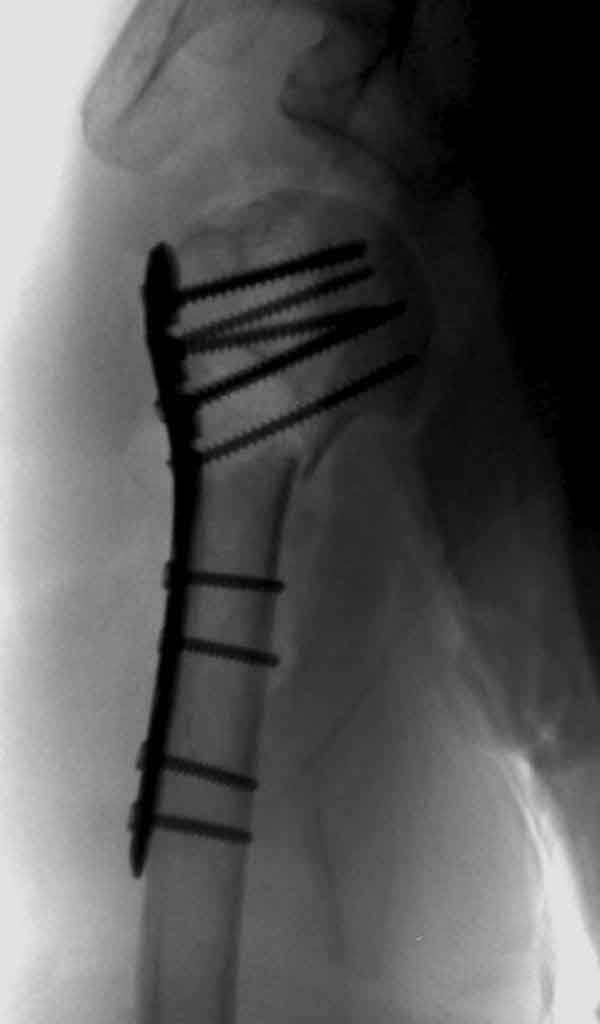

Здесь результат похожего случая, больная 87 лет, отягощенная сердечными делами и два года назад установка pacemaker и нескольких стентов. На третий день, сегодня утром сделали операцию. Послеоперационный псевдовывих связанный с релаксацией мышц и общим обезболиванием.

Имя     : humerus fx injury.JPG

Тип     : image/jpg

Размер  : 24112 байтов

Описание: отсутствует

Url     : http://weborto.net:8080/pipermail/ortho/attachments/20110611/5927b955/attachment-0007.jpg